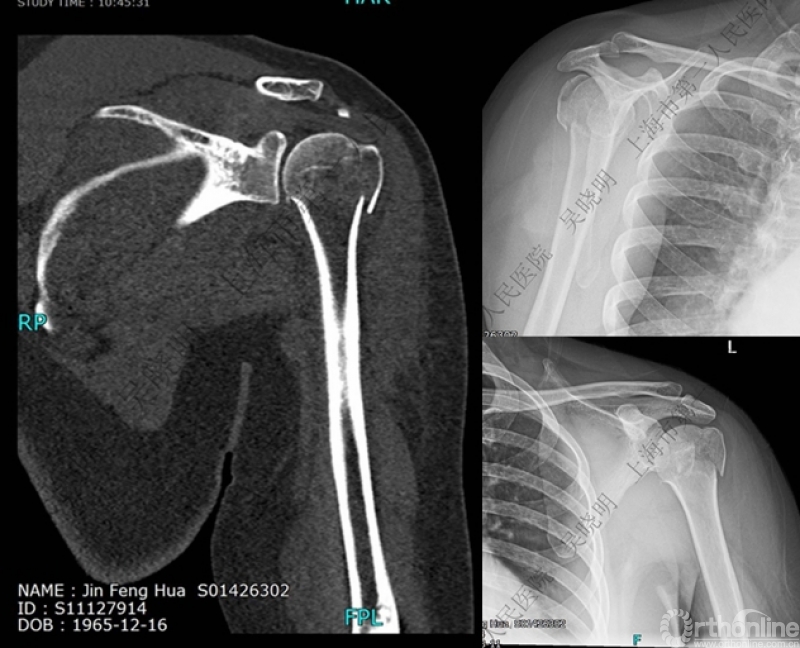

下图考虑为孤立性的大结节骨折?

看完片子,你会发现高质量的平片甚至3D CT也难以发现

X线看不清骨折线,三维CT也看不清

骨折线可以延伸到肱骨头

特别警惕伴肱骨头外翻合并大结节骨折的肩关节脱位

警惕:有无肱骨头外翻

伴大结节骨折的老年性肩关节前脱位伴肱骨头外翻

肩关节前脱位合并大结节骨折&肱骨头外翻:外翻压缩型(Neer 分型)

对这型骨折进行手法复位会导致肱骨头和肱骨干之间的连续性消失。肱骨头和肱骨干之间连续性尚存,肱骨头前脱位(Robsion 3b)

X线是孤立性向下移位的大结节,一定要小心,多伴有肱骨外科颈骨折